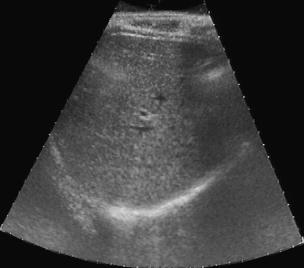

Most deep neural networks (DNNs) based ultrasound (US) medical image analysis models use pretrained backbones (e.g., ImageNet) for better model generalization. However, the domain gap between natural and medical images causes an inevitable performance bottleneck. To alleviate this problem, an US dataset named US-4 is constructed for direct pretraining on the same domain. It contains over 23,000 images from four US video sub-datasets. To learn robust features from US-4, we propose an US semi-supervised contrastive learning method, named USCL, for pretraining. In order to avoid high similarities between negative pairs as well as mine abundant visual features from limited US videos, USCL adopts a sample pair generation method to enrich the feature involved in a single step of contrastive optimization. Extensive experiments on several downstream tasks show the superiority of USCL pretraining against ImageNet pretraining and other state-of-the-art (SOTA) pretraining approaches. In particular, USCL pretrained backbone achieves fine-tuning accuracy of over 94% on POCUS dataset, which is 10% higher than 84% of the ImageNet pretrained model. The source codes of this work are available at https://github.com/983632847/USCL.

翻译:大部分深心神经网络(DNNS)基于超声波(美国)的超声波医学图像分析模型使用预先训练的脊椎(如图像网络)来进行更好的模型化分析。然而,自然图像和医疗图像之间的领域差距造成了不可避免的性能瓶颈。为了缓解这一问题,为在同一领域直接训练建造了一个名为US-4的美国数据集。该数据集包含来自四个美国视频子数据集的23 000多张图像。为了从美国-4中学习强健的特征,我们提议了美国半监督的对比学习方法,名为USCL(USCL),用于预培训。为了避免负面对子与有限的美国视频中丰富的地雷视觉特征之间的高度相似性,USCL采用了一种样品配对生成方法来丰富单步对比性优化所涉及的特征。关于一些下游任务的广泛实验显示了USCL对图像网络预培训和其他状态艺术预培训方法的优势。特别是,USCLU预先训练的骨架在POCS数据集上实现了94 %的微调精准性精确度,这在图像网络上比84%高10 %/MUSPASTASTASTRAIN premstrain practresmex pract press press rodustrismex sramduction sramduction sramduction sramduction surgles)。